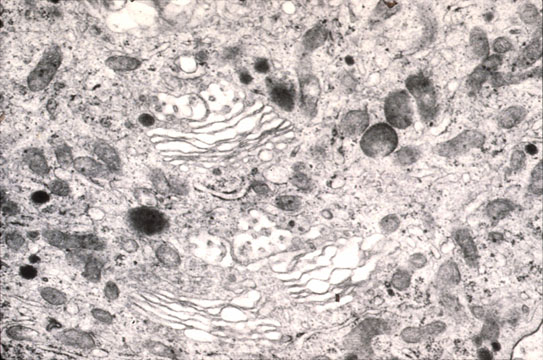

Cytoplasmic organelles Electron micrograph of a hepatocyte showing the cytoplasm with the various cytoplasmic organelles above described.

RER (rough) endoplasmic reticulum).Abundant and preponderant in zone 1 and 2 where the highest synthetic activity occurs,being the most oxygenated and nourished zones of the lobule.

SER (smooth) endoplasmic reticulum).Preponderant in zone 3,the area containing enzymes which attack drug (e.g. acetoaminophen) producing toxic radicals thus inducing centrolobular damage.

RIBOSOMES: Present in abundance as membrane bound,free and polyribosomes.

Golgi Complexes

Fig 22 - GOLGI COMPLEX:Curved stacks of parallel sachs with dilated bulbous ends which detach as vesicles loaded with lipo and glycoproteins to be discharged at the sinusoidal surface.The cis convex surface is the forming site while the trans concave surface is the secretory site.They are numerous and located toward the bile canaliculus.

MITOCHONDRIA: Numerous in hepatocytes.They supply energy.The sit of fat and carbohydrate metabolisim. They contain calcium granules and DNA(from the mother).They undergo division.

MICROBODIES: (Perixosomes) Single mebrane-bound particles,not vesicles with a granular matrix containing urate oxidase and delta-aminoacid oxidase. There is no urate oxidase in man because he is uricothelic.